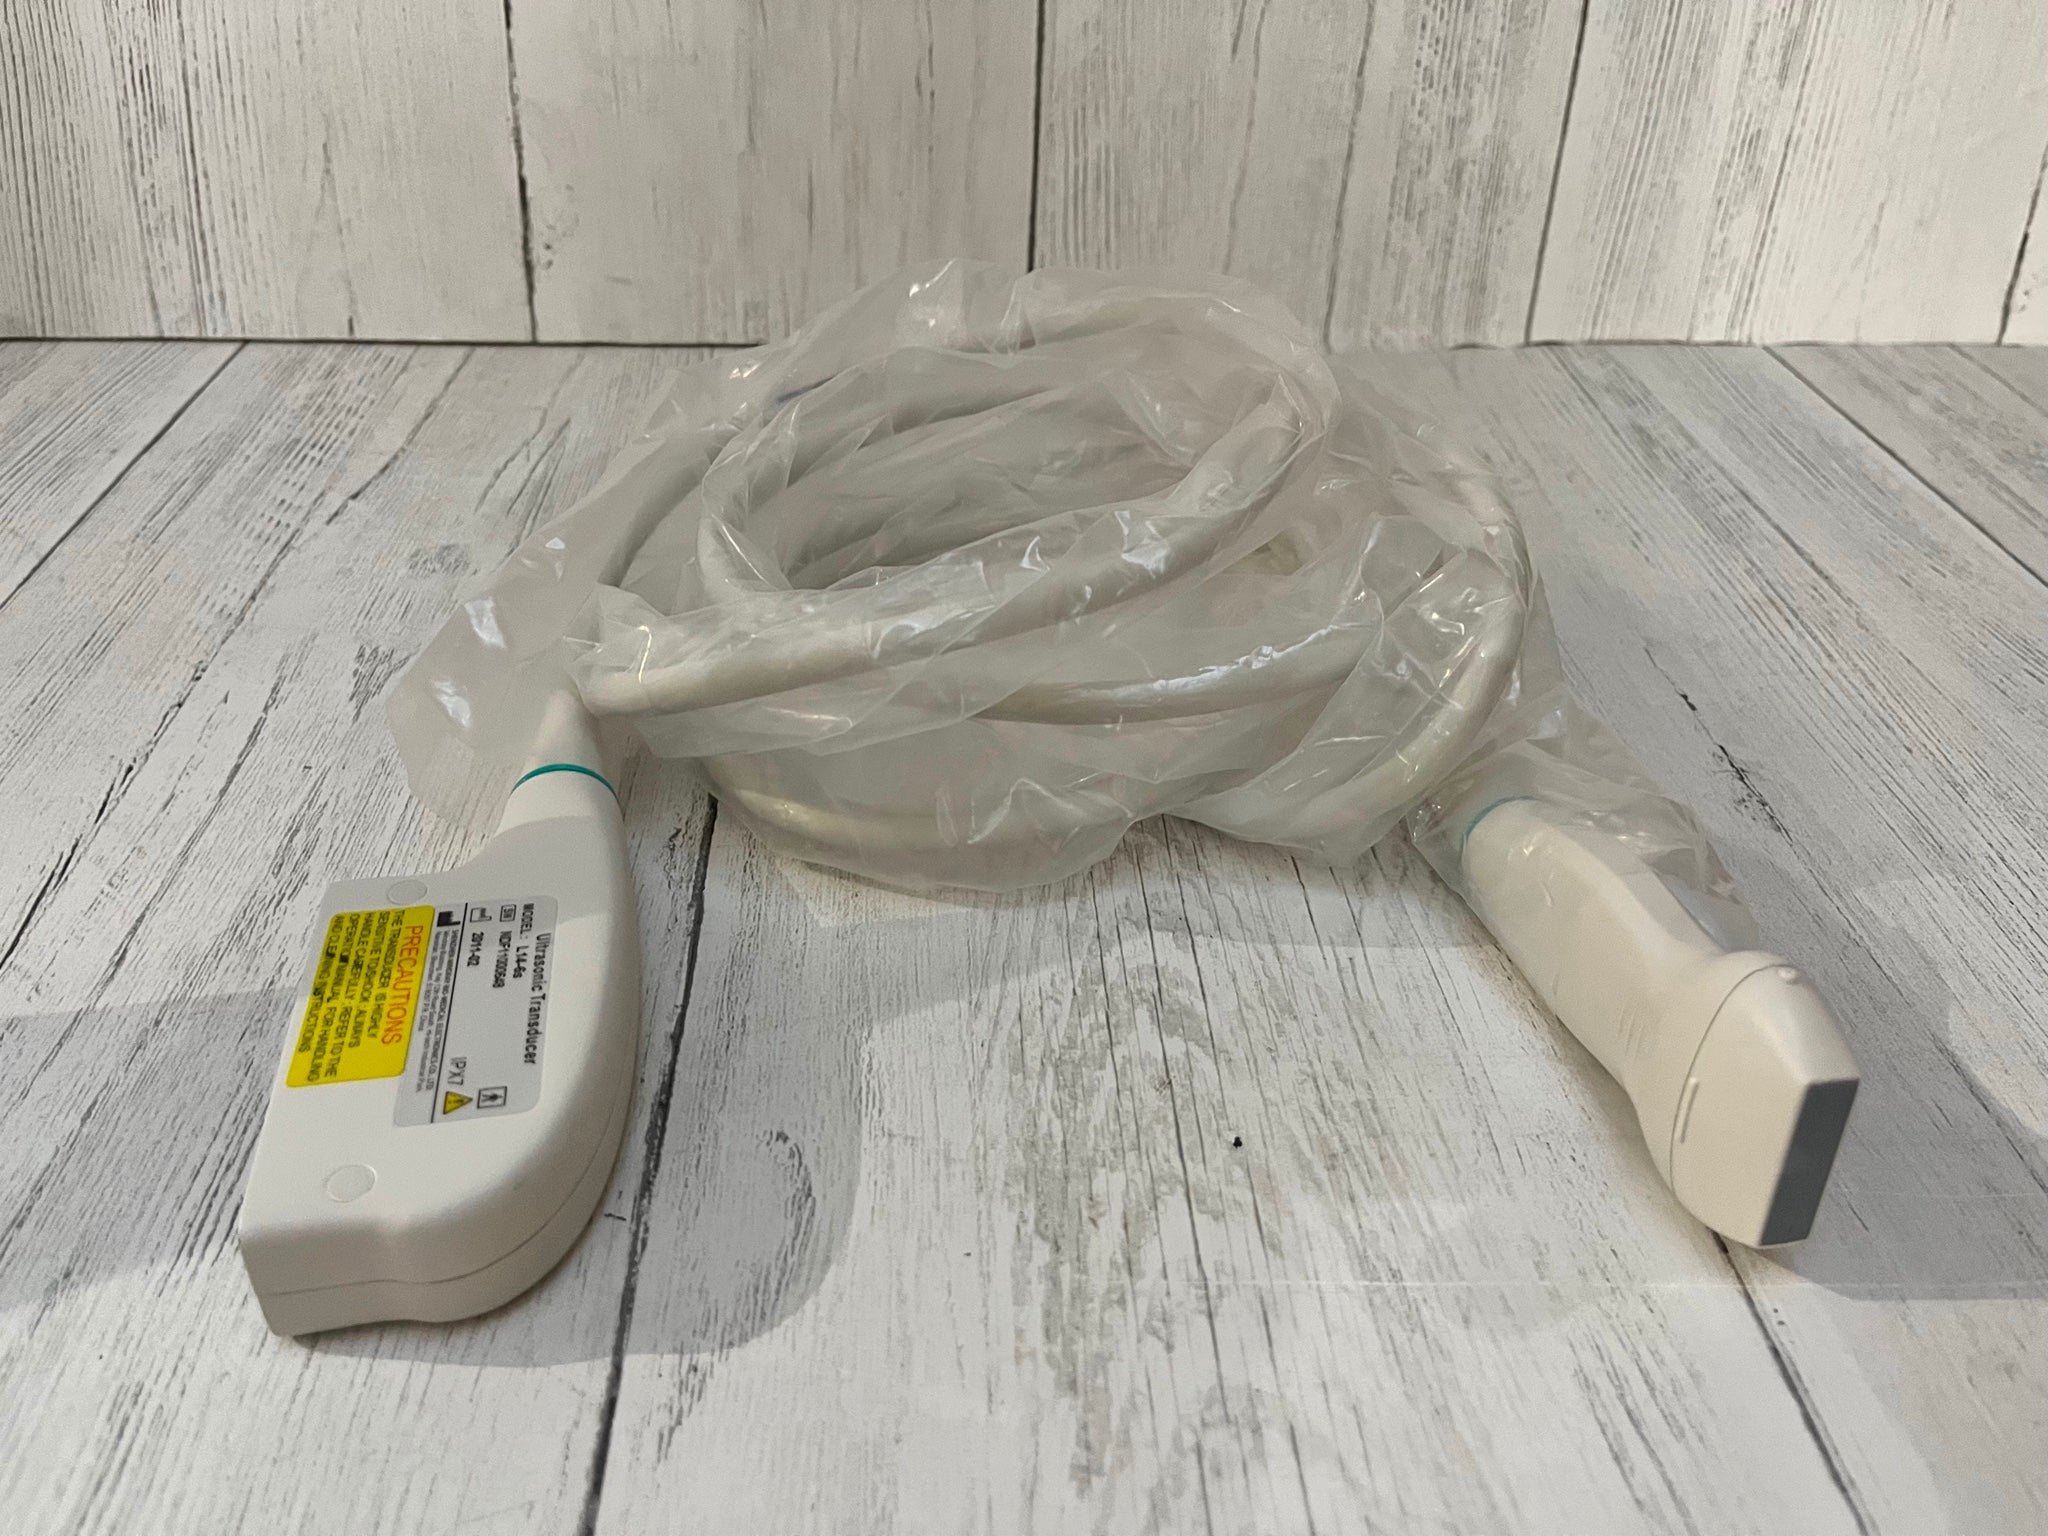

Description

Condition:Manufacturer refurbished : An item that has been professionally restored to working order by a manufacturer or manufacturer-approved vendor. This means the product has been inspected, cleaned, and repaired to meet manufacturer specifications and is in excellent condition. This item may or may not be in the original packaging. See the sellerâs listing for full details. See all condition definitions- opens in a new window or tab

Seller Notes:âGreat Condition!! - Manufacturer (GE) Refurbished!!â

Brand: LOGIQ E